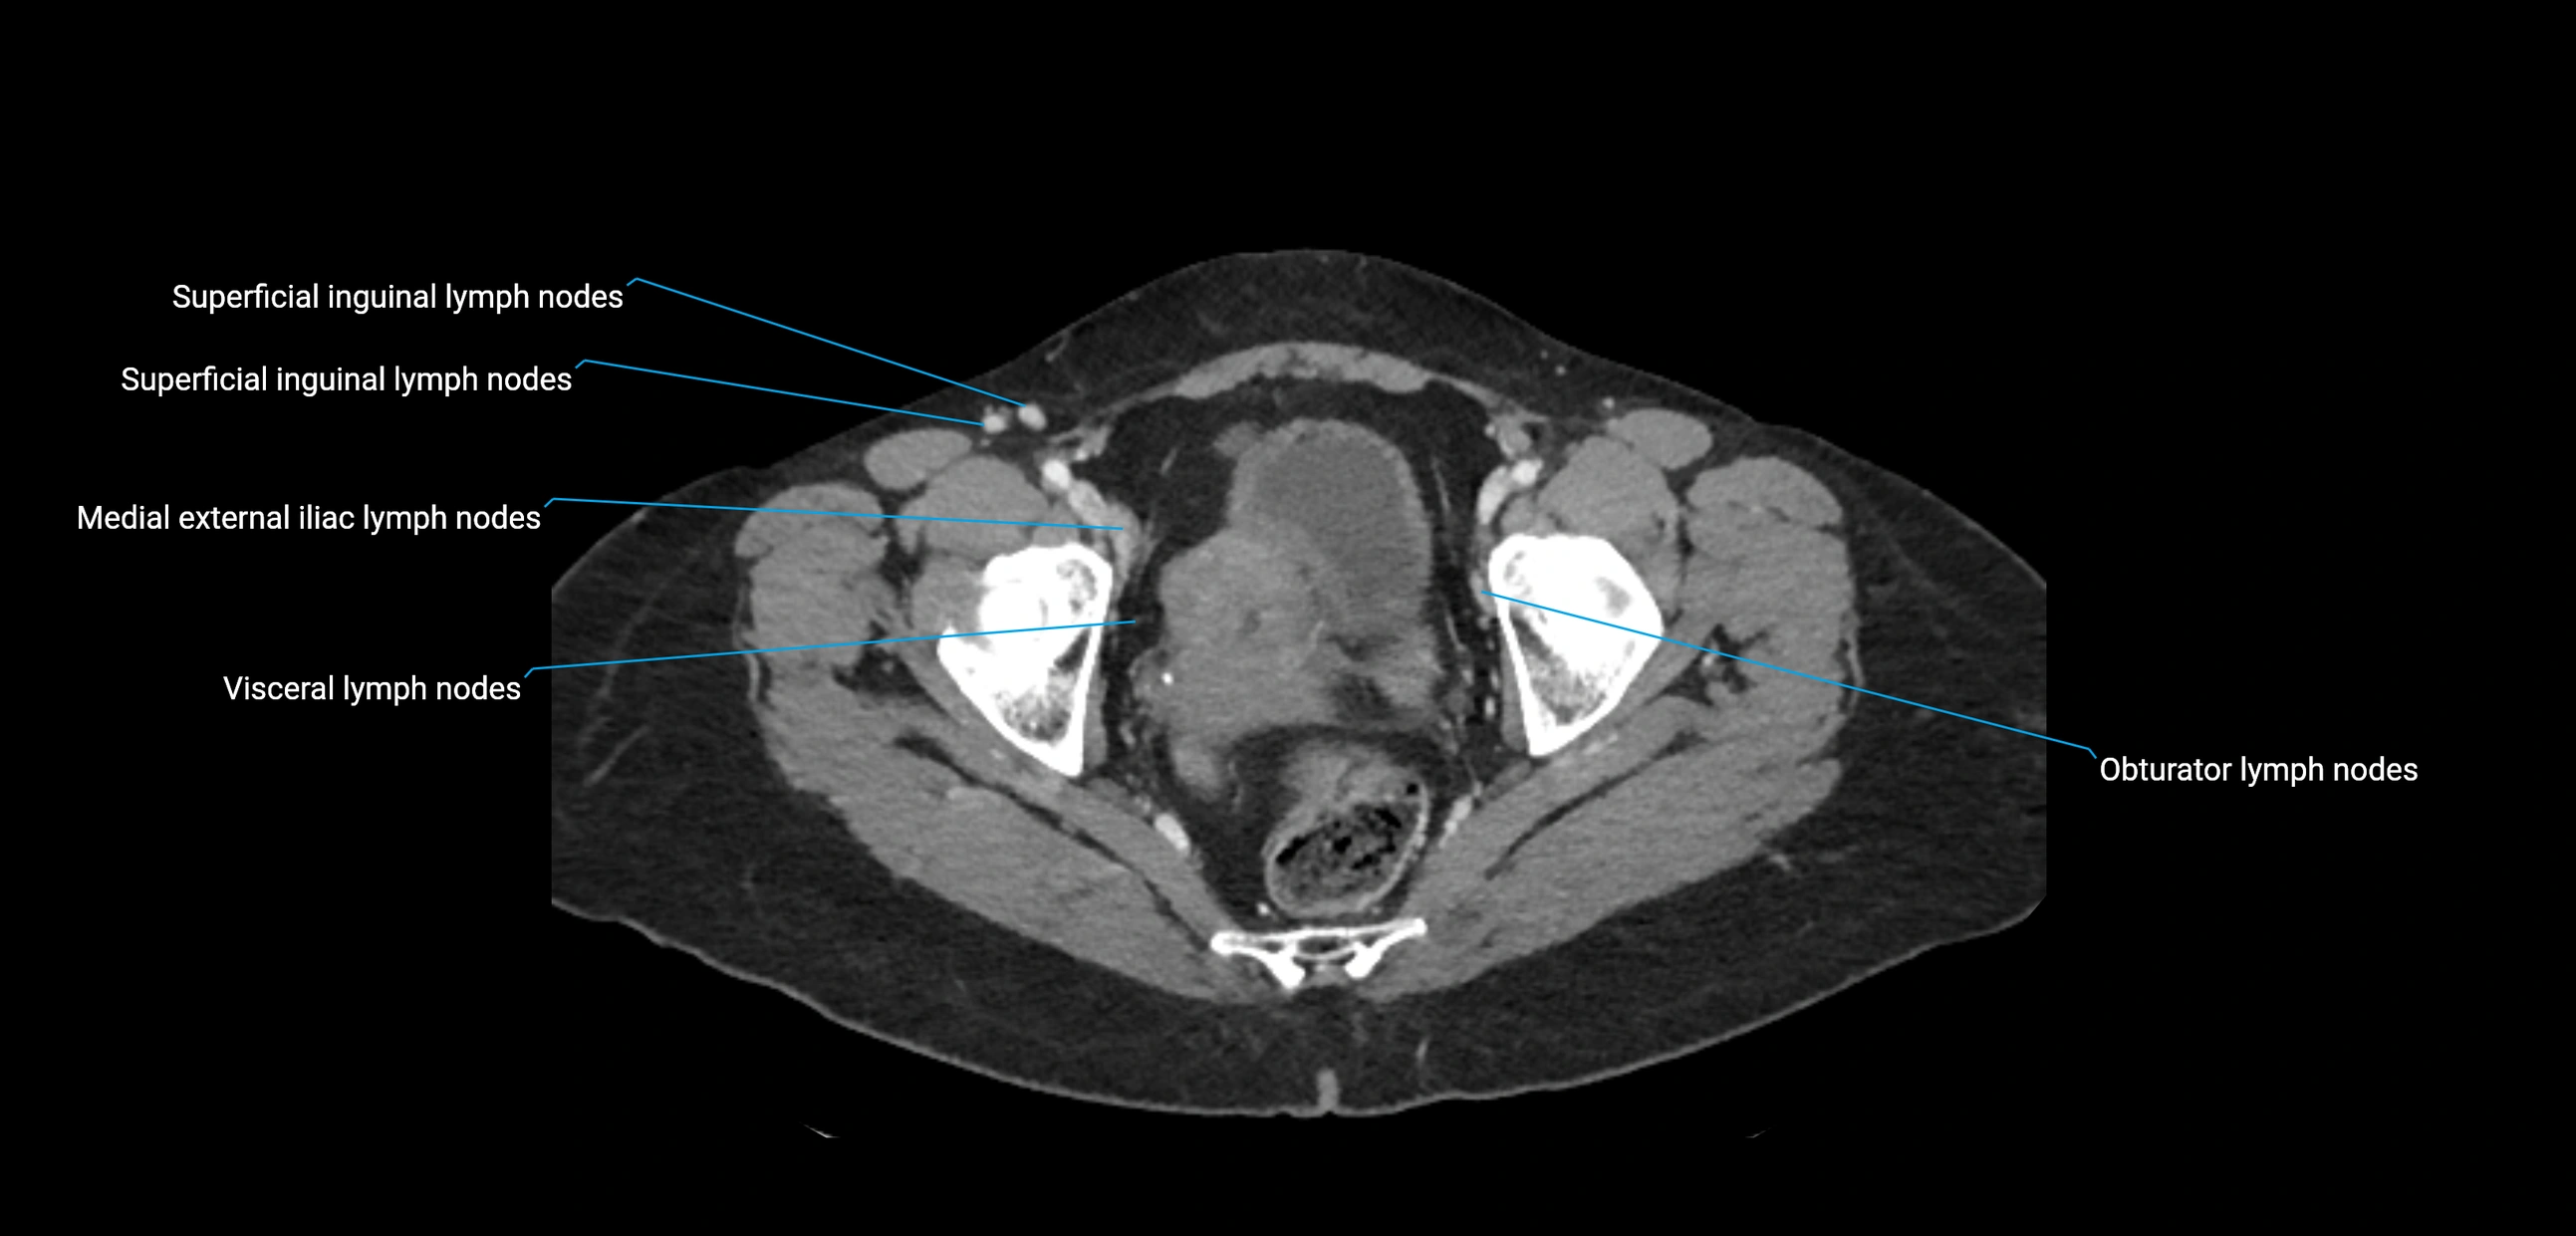

CT image

image